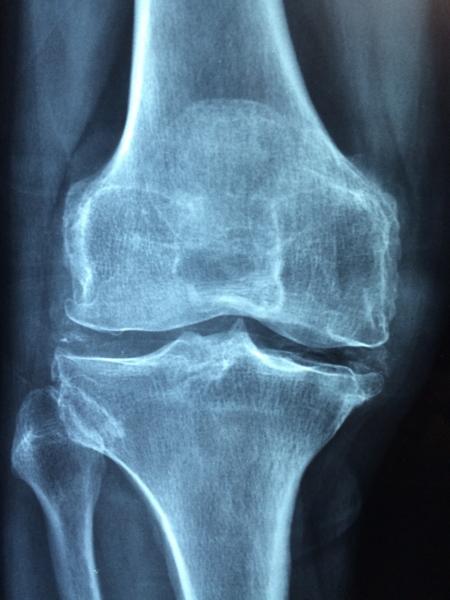

A Lyme-kór korai tünetei a fáradtság, láz, fejfájás és kiütés megjelenése. Ha nem ismerik fel időben a betegség tüneteit, akkor a baktérium eljuthat az ízületekbe, jellemzően a térd ízületeibe.

A reumatoid artritisz szintén egy autoimmun betegség, ami nőknél gyakrabban fordul elő, az esetek 75%-ában őket érinti. Az érzékeny, fájó ízületek és a reggeli ízületi merevség a rheumatoid artritisz tipikus tünetei. Emellett jelentkezhet fáradtság, láz és megmagyarázhatatlan testsúly csökkenés.